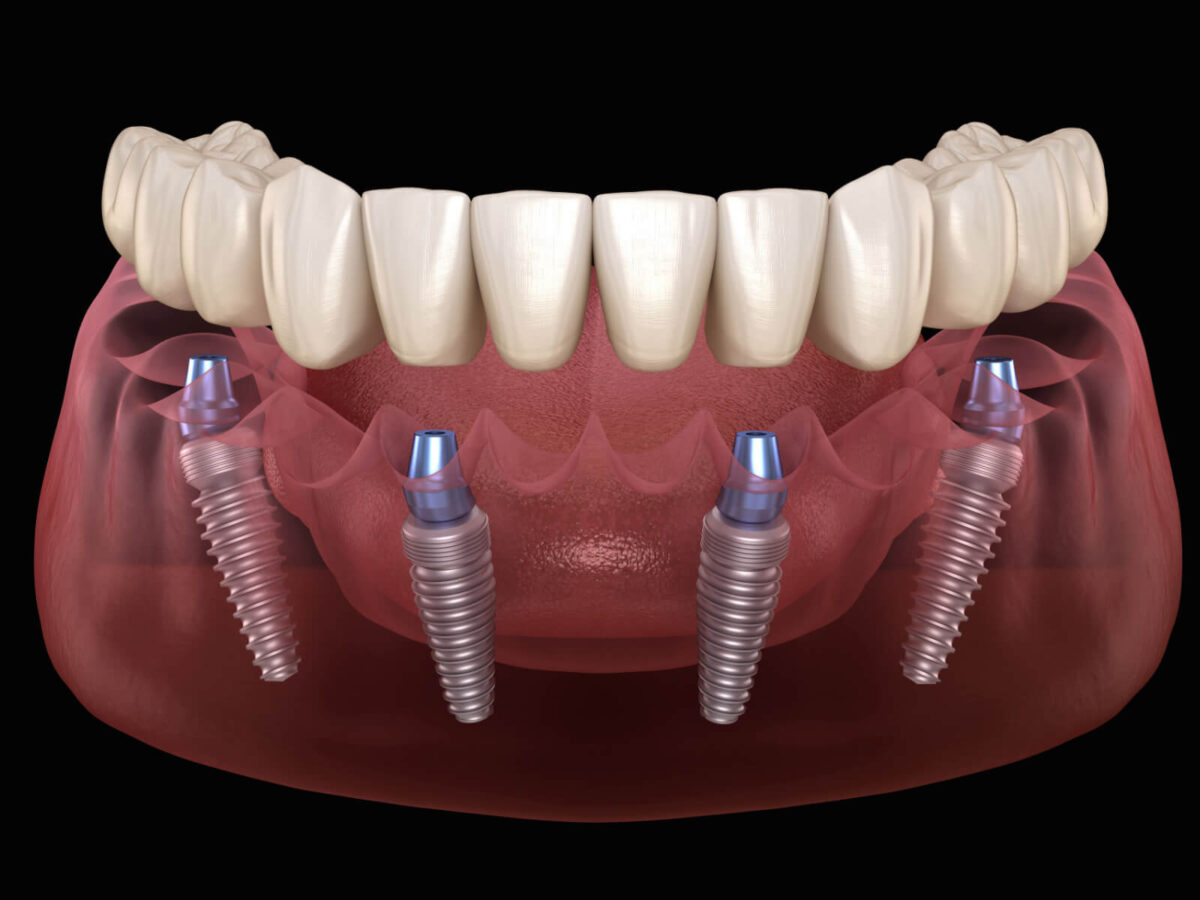

When your mouth is ready, we place the implant. This is a small metal post. It goes into the bone where the root of the tooth used to be. We use titanium because your body accepts it well.

The bone needs to connect with the implant. This is called osseointegration. It happens slowly and naturally. Most patients need a few months for this stage.

Step Five: Adding the Abutment

Once the implant is in place, we put on the abutment. It’s a tiny part that links the implant to the crown. It sits just above the gumline.